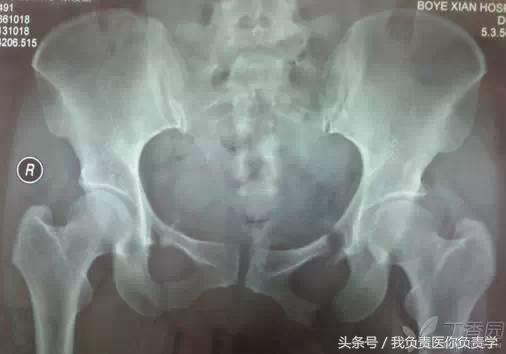

基本线标

(1)成人骨盆基本线标

a. 连接双侧髋臼顶端的连线,代表髋臼的上界及负重区。

b. 连接双侧大转子尖顶点的直线,正常通过双侧股骨头中心,一般用于股骨头置换术后股骨头高度的评价。

c. 连接双侧泪滴尖端的直线,代表双侧髋臼的最下缘,一般用于人工关节置换对髋臼假体位置的评价,正常时髋臼假体的内下缘紧贴此线的上缘。

d. 连接双侧坐骨结节下缘所成的直线,代表骨性骨盆的最下缘。

e. 连接双侧小转子下缘所成的直线,代表股骨近端最下缘。

f. 坐骨内缘与髂骨内缘的双切线,也称谓 Kohler 线(科勒氏线),代表髋臼的内侧界,一般用于髋关节置换中假体深度的评价,髋臼陷入症或髋关节置换骨质磨锉过深时髋臼突至此线内侧。

g. 经过耻骨联合的直线,为骨盆的对称轴。

h. 双侧髂骨最高点的连线,代表骨盆的最高点。

正常情况下,骨盆的六条水平线相互平行,且与经耻骨联合线垂直,当六条水平线出现不平行情况时,表示存在骨折错位或骨盆与髋臼的发育不良。